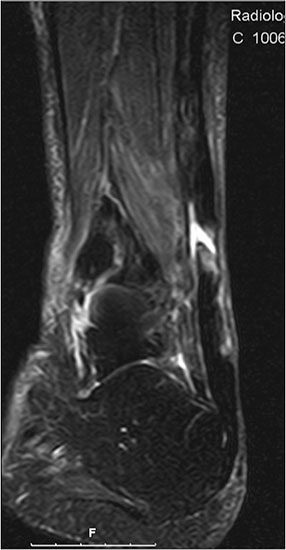

Der geübte Untersucher kann anhand des seitlichen Röntgenbildes die Diagnose einer Achillessehnenruptur stellen. Die Konturen des Kager-Dreiecks – gebildet von der ventralen Begrenzung der Achillessehne, der posterioren Tibiakante und der kranialen Kalkaneuskortikalis – verstreichen im Rupturfall (Kager 1939). Die MRT- Diagnostik spielt für die Primärdiagnostik der frischen Achillessehnenruptur eine untergeordnete Rolle und ist im Normalfall nicht notwendig. Anders verhält es sich bei den chronischen Rupturen. Hier ist die MRT ein wichtiges Diagnostikum insbesondere in Hinblick auf die Beurteilung der Sehnen- und Muskeldegeneration (Abb. 6).

Abbildung 6

Neben der strukturellen Wiederherstellung der Sehne ist die funktionelle Beurteilung des Muskels von entscheidender Bedeutung. Ist es bereits zu einer Degeneration der Muskeln gekommen, kann ein gutes funktionelles Ergebnis, trotz subtiler Sehnenrekonstruktion, nicht erreicht werden. Die Arbeitsgruppe um Hoffmann et al. 13 konnte in ihrer Arbeit zeigen, das es - ähnlich wie bei Patienten mit chronischen Supraspinatusrupturen - zu fettigen Degenerationen und Ödemen der Muskulatur kommt, die im MRT nachweisbar sind. Wir empfehlen die MRT- Untersuchung des gesamten Unterschenkels und nicht nur die rupturnahen Bereiche. Des Weiteren lässt die MRT eine Beurteilung der Degeneration der umliegenden Sehnenanteile zu. Die Computertomographie sollte nur in Ausnahmefällen zum Ausschluss von Begleitverletzungen (Abb. 7) durchgeführt werden und gibt uns sonst keinen weiteren Informationsgewinn.